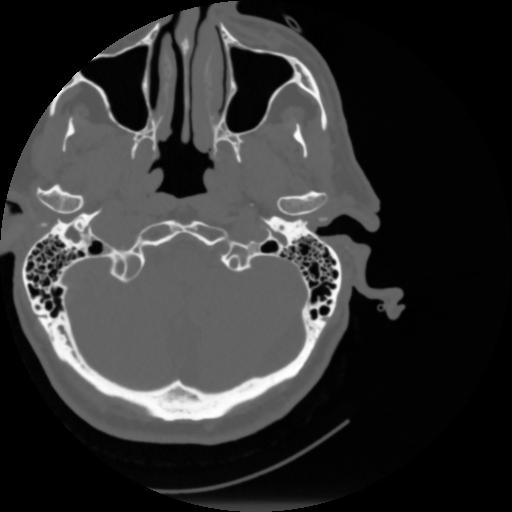

4 CEREBRO,,Vol,0.5,CEREBRO,,